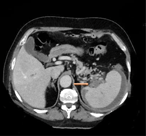

Spontaneous adrenal hemorrhage. Report of two cases and review of pathogenesis, diagnosis and management

Vasileios Charalampakis and others

Journal of Surgical Case Reports, Volume 2018, Issue 6, June 2018, rjy129, https://doi.org/10.1093/jscr/rjy129